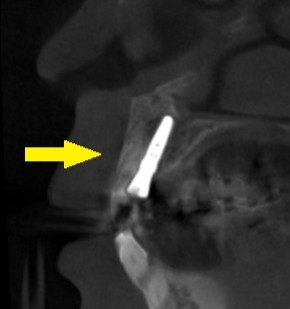

周囲骨の状態は問題ありませんでしたので、抜歯してそのままインプラント埋入を行う、抜歯即時埋入を行うことでご了承いただけましたので、本日、施行しました。

下の写真が、手術前後のCT画像です。